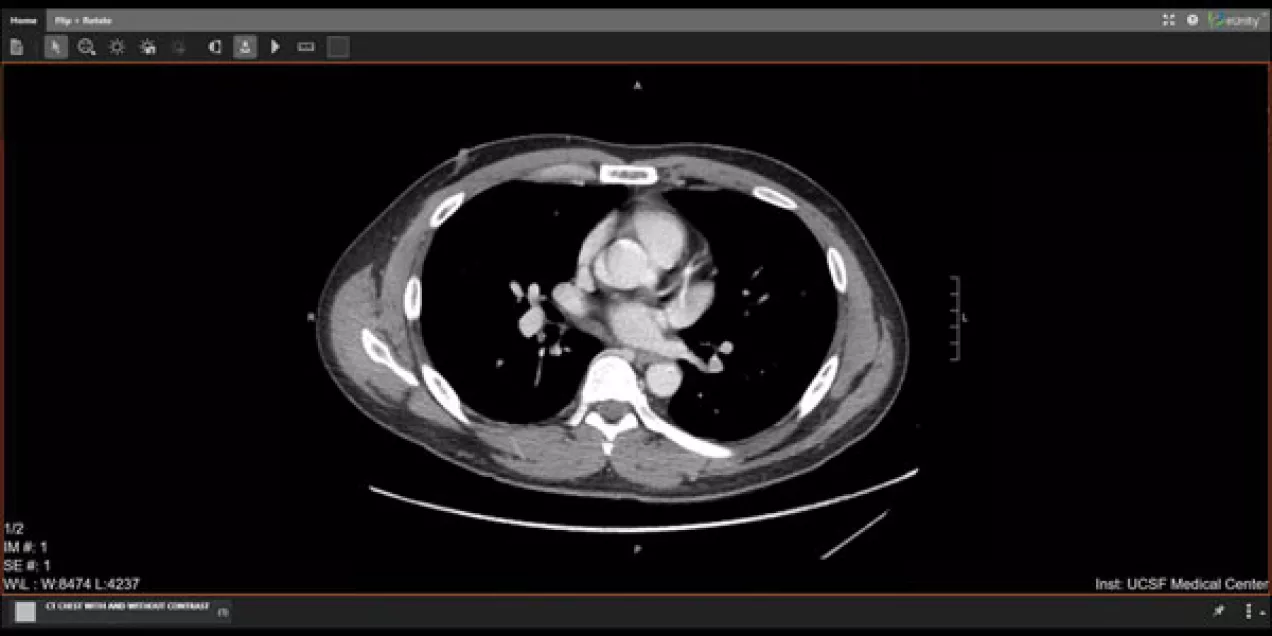

UCSF Patients Can Now Access Medical Images on MyChart

This month, UCSF Medical Center announced that patients can now see radiographic studies including X-rays, MRIs, CT scans and some ultrasounds on MyChart. Such a move is an additional step towards transparency and will allow patients to read reports and see images. We are the 19th Epic customer in the U.S. to use MyChart to make images available to patients, the second in California and the first University of California hospital.